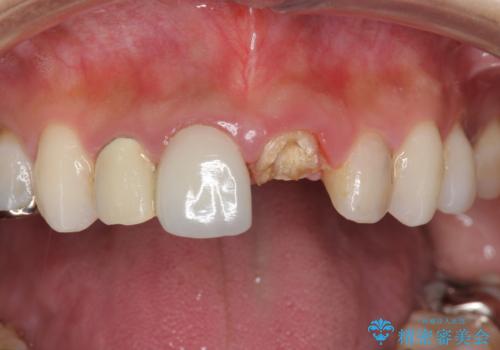

前歯が取れた

担当医 青山卓弘